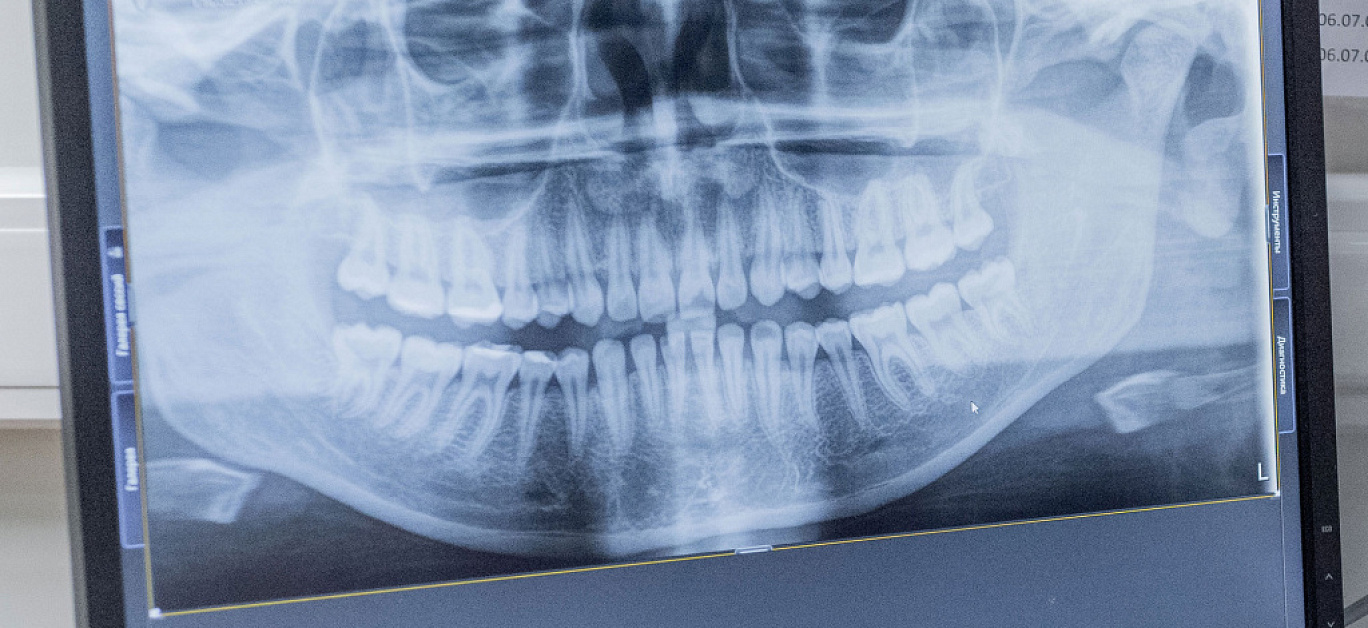

Аутотрансплантация зуба выполняется пациентам старше 21 года, когда завершено формирование костной ткани. Имплантируемый зуб должен быть здоровым, подходить по размеру и количеству корней. Это необходимое условие для успешного приживления зуба.

Перед операцией проводится профессиональная гигиена полости рта.

Пересадка зуба проводится поэтапно:

- введение анестезии;

- подготовка лунки и корневой системы для последующего вживления зуба;

- извлечение зуба-донора с небольшим объемом прилегающих мягких тканей путем деликатного надрезания;

- вживление зуба в подготовленную лунку;

- накладывание стоматологической шины для надежной фиксации вживленного зуба-донора.